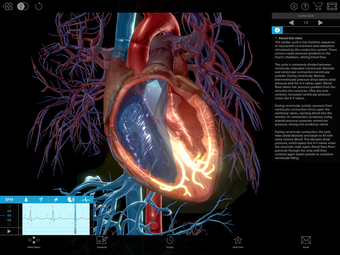

One of the most remarkable features of this application is that it enables users to compare 3D models of normal anatomy with models of common diseases and conditions. Furthermore, users can set the heart rate and visualize conduction in a dissectable, beating 3D heart while following along on an ECG. The application also presents animations that demonstrate the physiological processes of gas exchange, pulmonary ventilation, fluid balance, peristalsis, and more. Interactive lessons walk users through the progression of atherosclerosis, kidney stones, lung cancer, and other common conditions, and quizzes test users' knowledge of various physiological processes and pathologies.